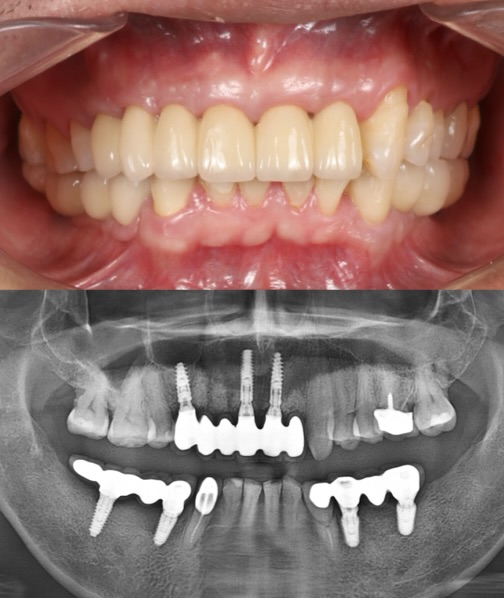

FULL MOUTH REHABILITATION

This case showcases a complete smile transformation for a patient with severe bruxism (teeth grinding). Through expert planning, full zirconia crowns were used to rebuild worn teeth, while dental implants were placed in the lower back for long-term strength and stability. The Work done at Moral Dental Clinic, the result is a durable, natural-looking smile—restored in both form and function.